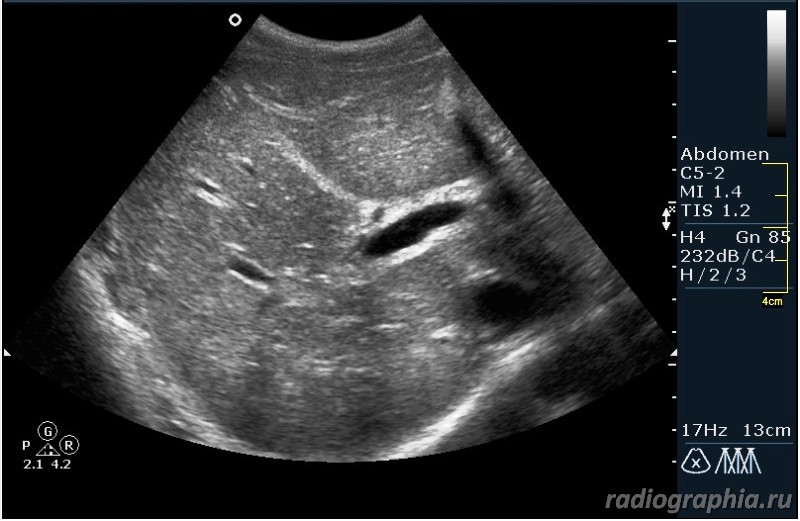

Как вы думаете, при какой патологии можно наблюдать такую сонографическую картину?

Похоже на расширенные внутрипеченочные протоки ,отек стенок ж.пузыря--может быть при остром гепатите

Гепатиты - такой ответ автор считает верным.